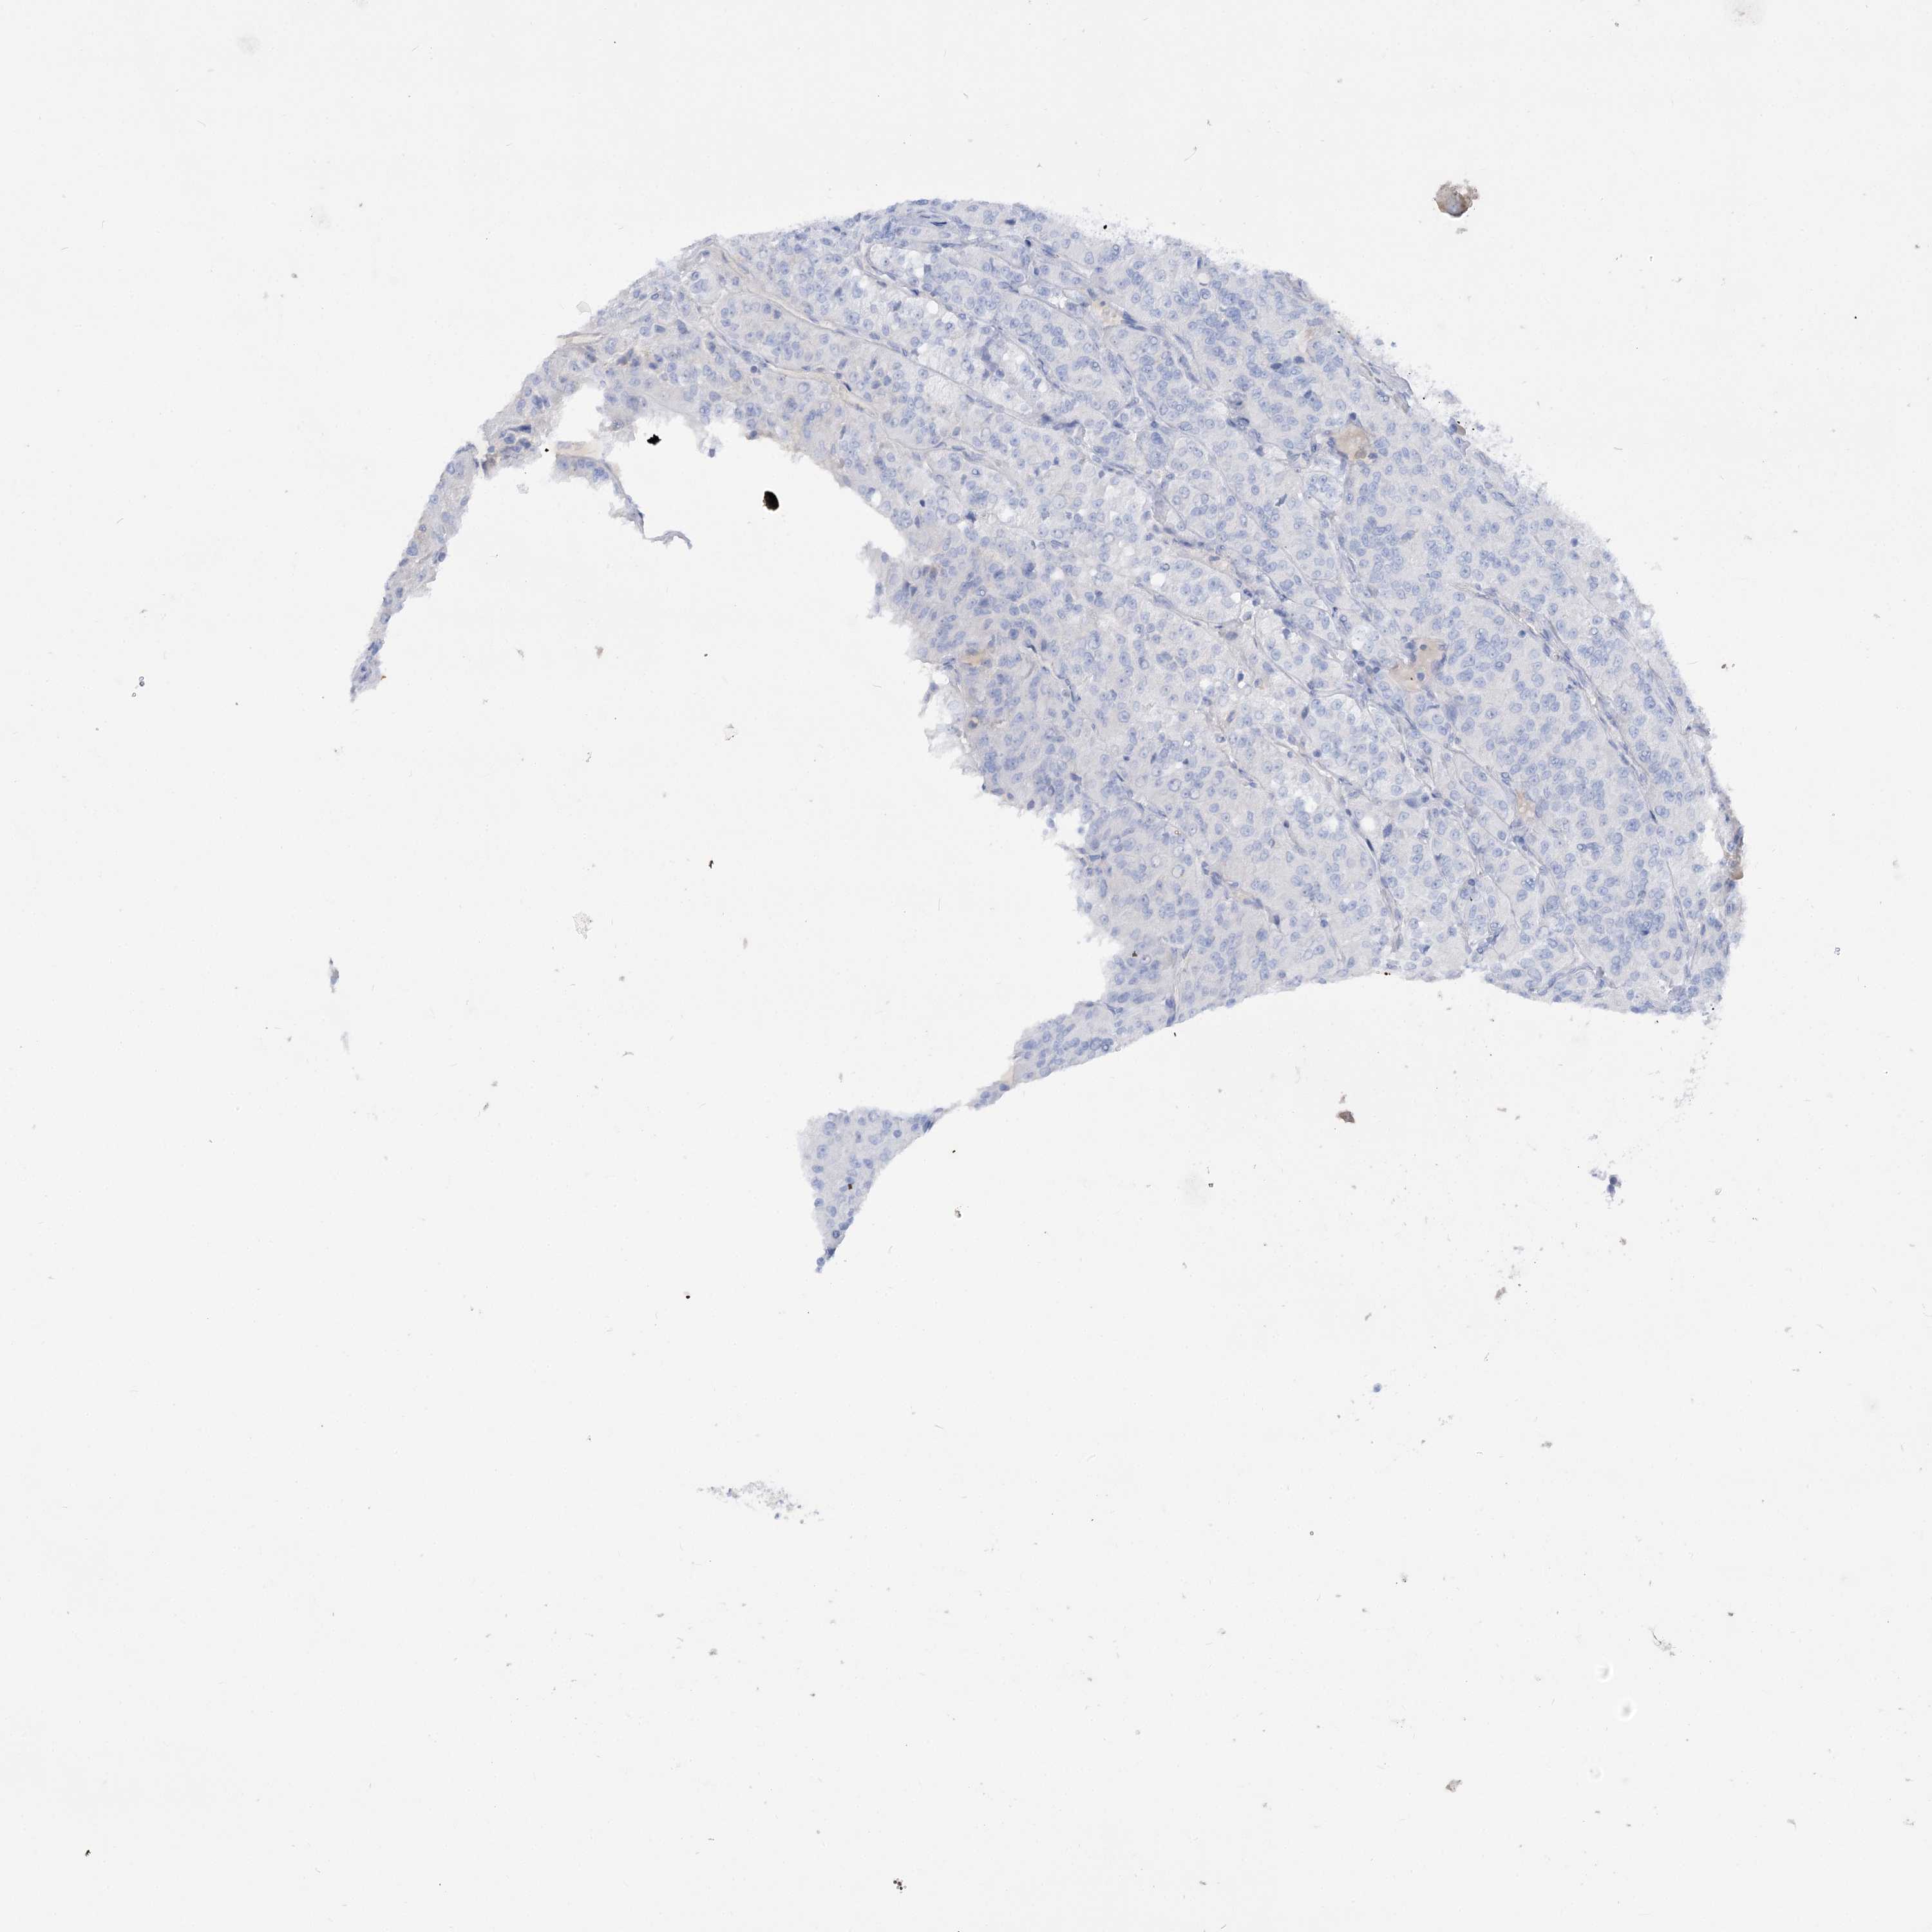

KIDNEY RENAL PAPILLARY CELL CARCINOMA (TCGA) - Interactive survival scatter ploti

The Survival Scatter plot shows the clinical status (i.e. dead or alive) for all individuals in the patient cohort, based on the same data that underlies the corresponding Kaplan-Meier plots. Patients that are alive at last time for follow-up are shown in blue and patients who have died during the study are shown in red.

The x-axis shows the expression levels (FPKM) of the investigated gene in the tumor tissue at the time of diagnosis. The y-axis shows the follow-up time after diagnosis (years). Both axes are complimented with kernel density curves demonstrating the data density over the axes. The top density plot shows the expression levels (FPKM) distribution among dead (red) and alive patients (blue). The right density plot shows the data density of the survived years of dead patients with high and low expression levels respectively, stratified using the cutoff indicated by the vertical dashed line through the Survival Scatter plot. This cutoff is automatically defined based on the FPKM cutoff that minimizes the p-score. The cutoff can be changed by dragging the vertical line or by entering a cutoff value in the square labeled "Current cut-off".

Under the Survival Scatter plot the p-score landscape (black curve; left axis) is shown together with dead median separation (red curve; right axis). Dead median separation is the difference in median mRNA expression between patients who have died with high and low expression, respectively. It is calculated as follows: median FPKM expression of dead patients with high expression - median FPKM expression of dead patients with low expression. This is intended to aid the user in visually exploring custom cutoffs and the associated p-scores and dead median separation.

Individual patient data is displayed and can be filtered by clicking on one or more of the category buttons on the top of the page. Categories describing expression level and patient information include: high, low, alive, dead, female, male and tumor stages. The scale of the x-axis can be toggled between linear and log-scale by clicking on the "x log" button. Mouse-over function shows TCGA ID, patient information and mRNA expression (FPKM) for each patient.

& Survival analysisi

Kaplan-Meier plots summarize results from analysis of correlation between mRNA expression level and patient survival. Patients were divided based on level of expression into one of the two groups "low" (under cut off) or "high" (over cut off). X-axis shows time for survival (years) and y-axis shows the probability of survival, where 1.0 corresponds to 100 percent.

GBF1 is not prognostic in Kidney Renal Papillary Cell Carcinoma (TCGA)

Best expression cut offi